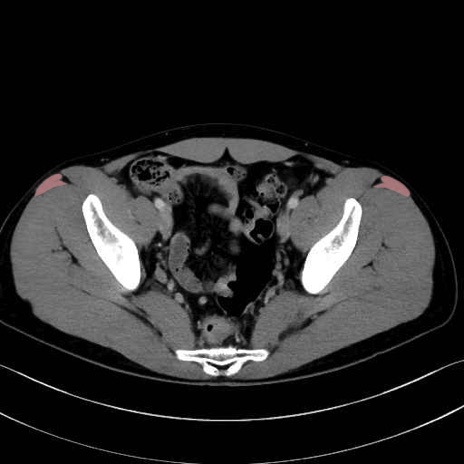

大腿筋膜張筋 (Tensor fasciae latae)